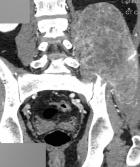

K.M. - 42 year old male c/o a sharp, moderate, constant pain in his lower back radiating down his LLE for four months. He reports some LLE weakness, which does not limit his ambulation. He has also noticed a bulge around his left pelvis. No F/C.

Zoom image: Radiological image Radiological image.